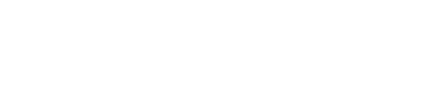

Crianças com a síndrome do bebê sacudido frequentemente apresentam hemorragias retinianas em várias camadas, com riscos de descolamento de retina, retinosquise macular e hemorragias vítreas, dependendo do impacto do trauma craniano. Danos permanentes à visão podem resultar de lesões diretas nos olhos ou no cérebro, sendo a última a principal causa de deficiência visual. Cicatrizes retinianas e atrofia do nervo óptico são geralmente irreversíveis e podem aparecer meses após a lesão. As constatações oftalmológicas podem oferecer dados diagnósticos significativos à equipe multidisciplinar, especialmente em situações em que há poucos indícios externos de abuso. O presente estudo relata o caso de uma criança com 2 meses de vida admitida em pronto-socorro oftalmológico e diagnosticado com síndrome do bebê sacudido.